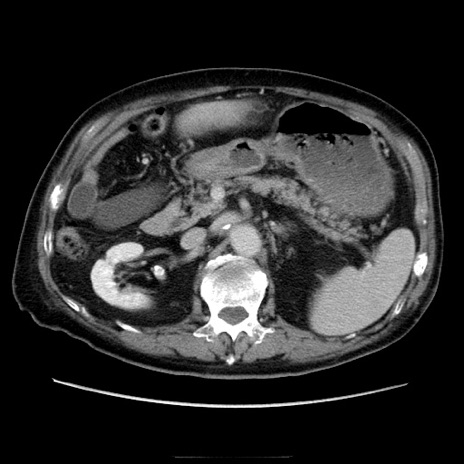

症例21(横断像)

【症例】70歳代男性

【主訴】腹痛

【現病歴】肝硬変・肝細胞癌にてかかりつけの方。約9時間前に食後より腹痛出現。症状が徐々に増悪し、嘔吐出現したため来院。

【既往歴】肝硬変、肝細胞癌(RFA、TACE後)

【身体所見】意識清明、表情苦悶様、BT 36℃、BP 129/78mmHg、P 88bpm、SpO2 97%(RA)、右上腹部から心窩部にかけて圧痛あり、反跳痛なし、筋性防御あり。

【データ】WBC 5800、CRP 0.16